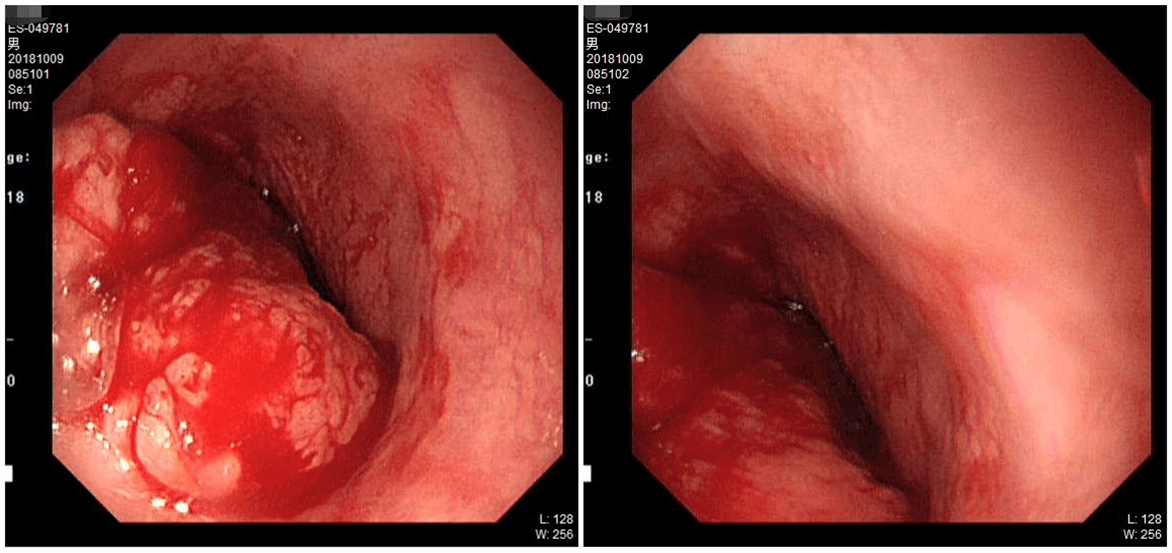

现病史:患者1年前出现进食梗咽,有近期明显消瘦,有纳差,无恶心、呕吐,无呛 咳,无胸背痛,无呕血、黑便,查胃镜示:距门齿825px新生物;病理:(食管)浅表粘膜鳞状上皮高级别上皮内瘤变。

胃镜:距门齿825px新生物;病理:(食管)浅表粘膜鳞状上皮高级别上皮内瘤变。